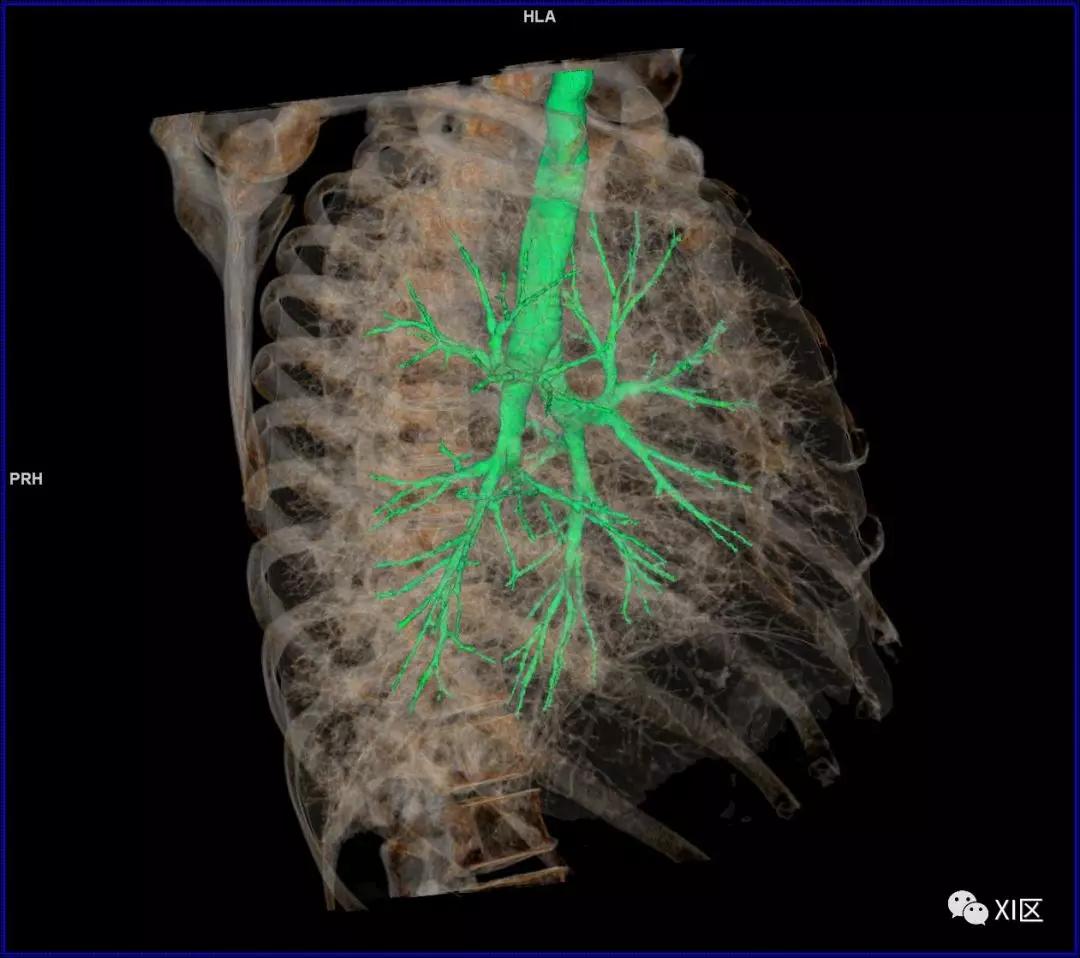

前后位,双侧位,后前位显示气道肺与胸部骨骼的关系

气管支气管树与两肺融合显示